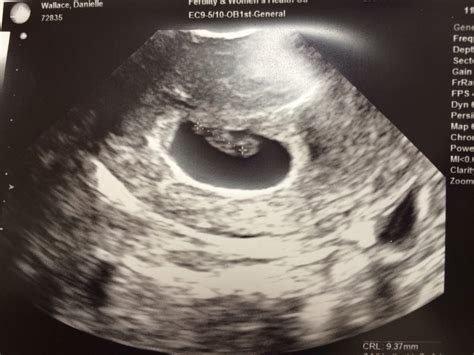

A 7 week pregnancy sonography is typically performed transvaginally, as the uterus is still relatively small at this stage. This method provides a clearer image of the developing embryo. The ultrasound technician will use a wand-like device covered with a condom and lubricated with gel, which is gently inserted into the vagina. The procedure is generally painless and takes only a few minutes.

• The embryo itself, which should be visible as a small, curved structure within the gestational sac.

• The fetal pole, which is the earliest visible part of the embryo.

• The heartbeat, which may be detectable by this week, although it is not always visible at 7 weeks.

If the heartbeat is not detected, it is not necessarily a cause for concern, as it can sometimes be too early to see. The technician will also measure the size of the gestational sac and the crown-rump length (CRL) of the embryo, which helps to estimate the gestational age and ensure that the pregnancy is progressing normally.

At 7 weeks, the embryo is still very small, measuring about 10,000 times smaller than a newborn baby. However, significant development is occurring. Some of the common findings during a 7 week pregnancy sonography include:

• The embryo is curved, with a distinct head and tail.

• The neural tube, which will eventually form the brain and spinal cord, is beginning to close.

• The heart is developing rapidly, and the heartbeat may be visible.

• The placenta is starting to form, providing essential nutrients and oxygen to the embryo.